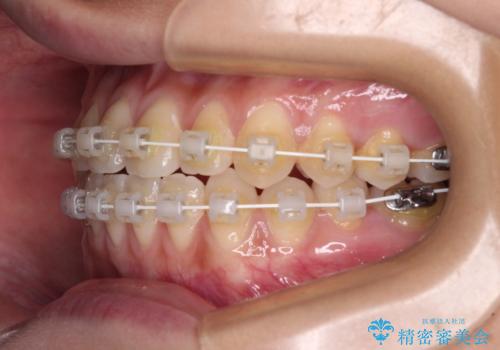

- 矯正装置

- 審美装置

クロスバイト改善まではスムーズに進みましたが、その後は強い舌の突出癖によりオープンバイトの期間が長く続きました。

舌のトレーニングをしっかりと実施してもらい、何とか仕上げることができました。